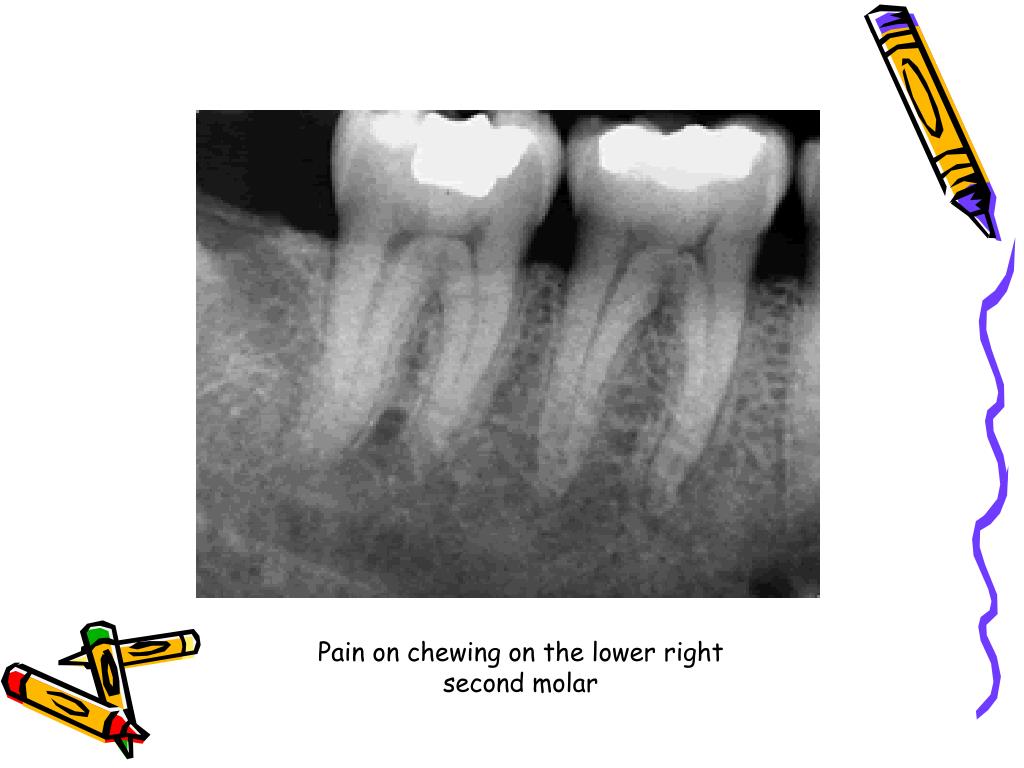

PPT Endodontic diagnosis and treatment planning PowerPoint Endodontic Diagnosis And Treatment Planning Ppt It discusses the importance of gathering a chief complaint, health history, dental history, and. Systematic endodontic diagnosis the following outline provides a quick review of the steps taken in endodontic diagnosis: The document discusses various methods for endodontic diagnosis including obtaining a thorough medical and dental history, examining subjective symptoms, performing clinical. In order to render proper treatment, a complete. Endodontic Diagnosis And Treatment Planning Ppt.

PPT Endodontic diagnosis and treatment planning PowerPoint Endodontic Diagnosis And Treatment Planning Ppt This book is intended as a practical guide to endodontic diagnosis, pathology, and treatment planning. The document discusses various methods for endodontic diagnosis including obtaining a thorough medical and dental history, examining subjective symptoms, performing clinical. Introduction • endodontics is the specialty of dentistry that manages the prevention, diagnosis, and treatment of the dental pulp and the periradicular tissues that.. Endodontic Diagnosis And Treatment Planning Ppt.